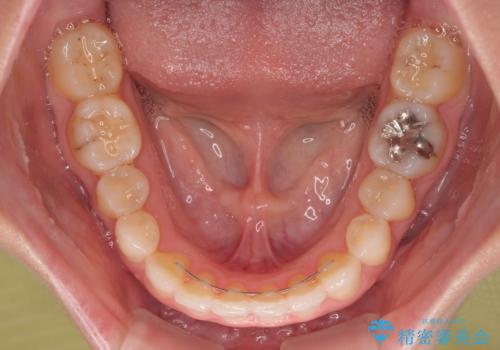

前歯のデコボコと小さい歯を改善 インビザラインとオールセラミッククラウン

- 前歯のデコボコと左右の矮小歯を気にして来院された患者様です。

矮小歯の前後にスペースを作るようにインビザライン矯正治療を計画し、矯正治療後にオールセラミッククラウンによる補綴治療を行うこととしました。

アンカースクリューを用いて上顎歯列全体を後方移動させ、極力過蓋咬合も改善されるよう計画しました。

インビザラインは長時間装着を自己管理する必要がありますが、残念ながら十分な時間の装着を行うことができませんでした。

何とか矮小歯を改善するスペースを作ることはできましたが、過蓋咬合を改善するには至りませんでした。